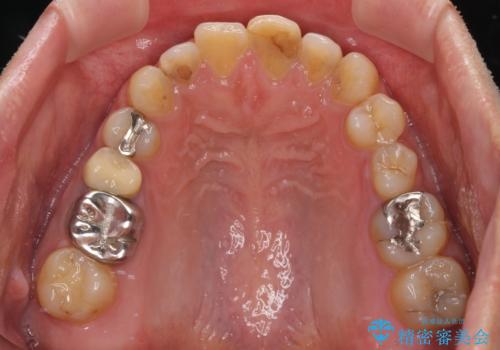

- 前歯の色を気にして来院された患者様です。

むし歯で神経が取り除かれており、歯の変色と充填材の変色などにより、つぎはぎのような前歯となっていました。

膿の出口も認められたため、まずは根管治療を実施し、オールセラミッククラウンにて補綴治療を行うこととしました。